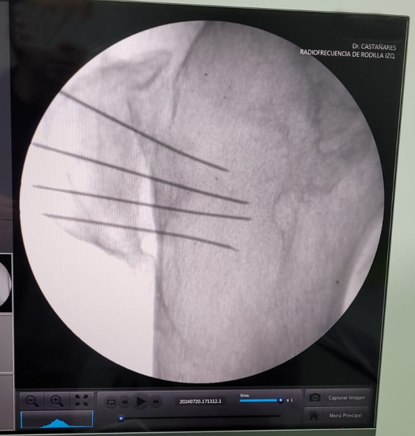

En Tidol tratamos el caso de un paciente de 90 años, con artrosis severa de rodilla izquierda.

El paciente presentaba limitaciones de reemplazo total de rodilla y no se le podía realizar la cirugía por osteoporosis y comorbilidad; por lo que se decidió realizar tratamiento con radiofrecuencia de los nervios geniculados.